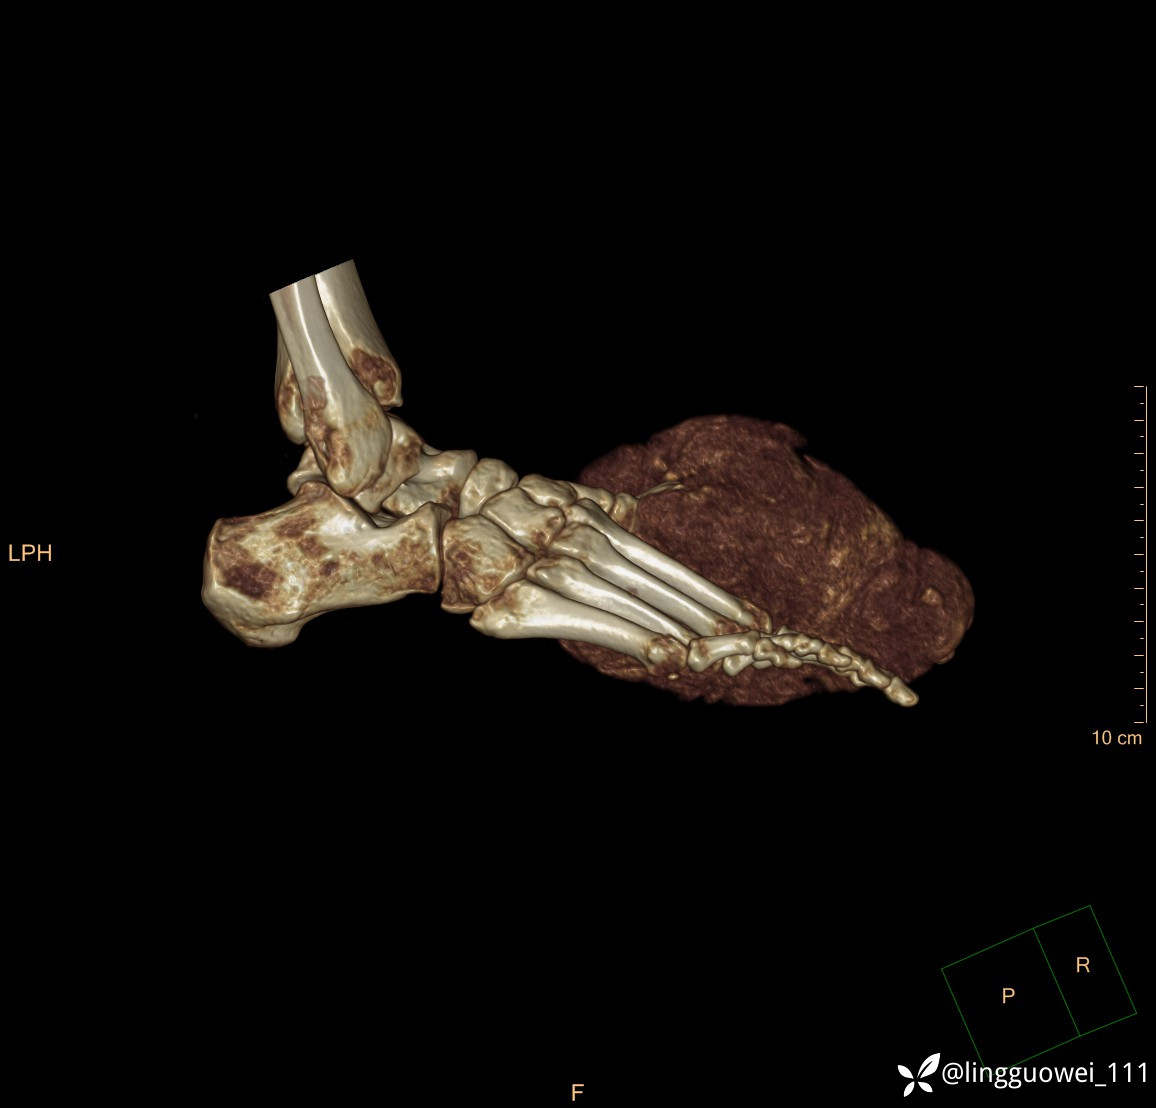

患者于2年余前高嘌呤饮食及大量饮酒后出现全身多处关节痛风石,以右足第一跖趾关节和右手为显,局部红肿热痛反复发作,自行口服药物后可缓解(药物可疑为强的松、双氯芬酸钠等,具体不详)。2年来右足痛风石明显增大,约10cm*5cm*15cm,局部红肿发热,3天前患者再次大量饮酒后痛风石顶部破溃,可见4cm*3cm皮损,较多白色豆渣样分泌物流出,为求进一步治疗来诊,门诊诊断为“右足痛风石破溃伴感染”, 收住院拟手术治疗,患者起病以来,无发热,精神佳、胃纳好、睡眠佳,大小便正常。

专科检查:右足外观畸形,足背部可见巨大痛风石形成,痛风石大小约10cm*5cm*15cm,局部皮肤红肿发热,痛风石顶部破溃,可见4cm*3cm皮损及白色豆渣样分泌物流出;痛风石界限清,质偏硬,局部触及波动感,无压痛,移动度差。右足踇趾及第2趾被痛风石压迫,关节活动受限。肢端血运、感觉无异常。 右手稍肿胀,2-5指背侧可见多发痛风石形成,最大者约花生米大小,皮肤完整未破溃,痛风石界限清,质偏硬,局部触及波动感,无压痛,移动度差。